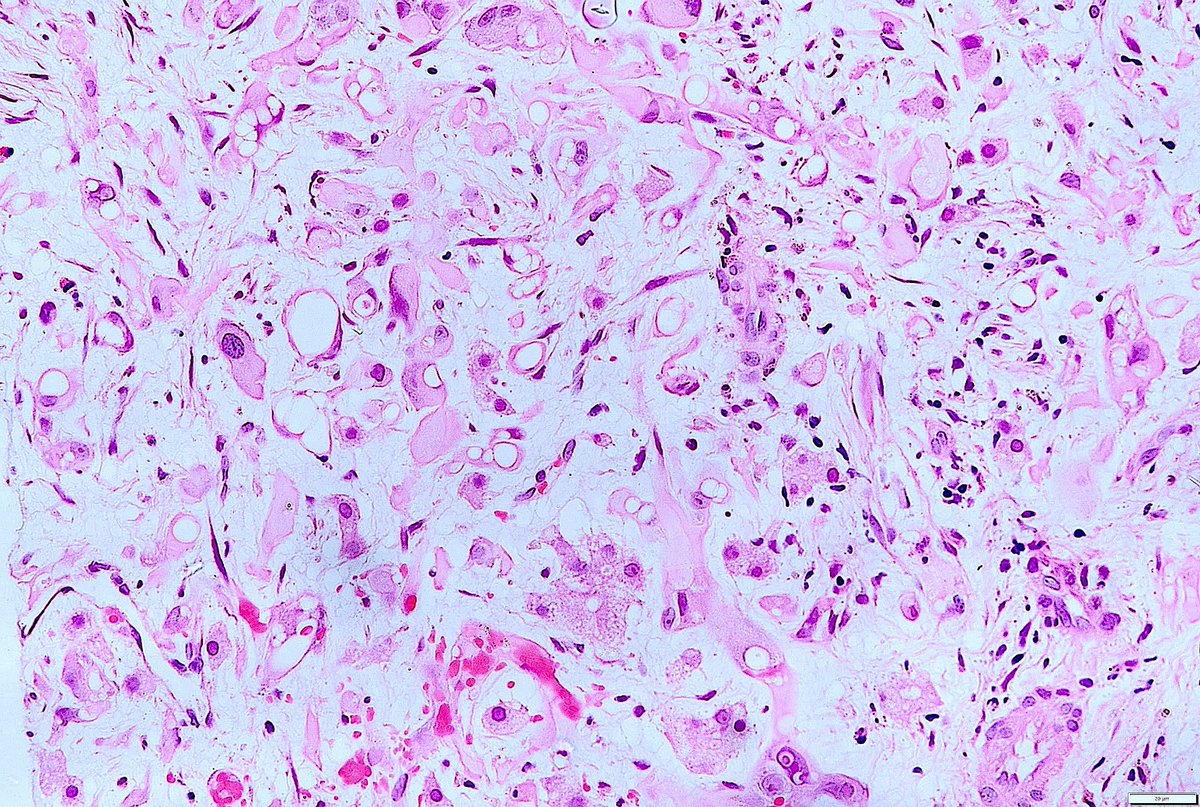

What is this bubbly cell? What are the pink dots in the cytoplasm? Diagnosis? Answers ✅ youtu.be/DqLK6ZvNXTU #pathology #pathologists #pathTwitter #dermpath #dermatology #dermatologia #dermtwitter

What is this bubbly cell? What are the pink dots in the cytoplasm? Diagnosis?

Answers ✅ youtu.be/DqLK6ZvNXTU

#pathology #pathologists #pathTwitter #dermpath #dermatology #dermatologia #dermtwitter